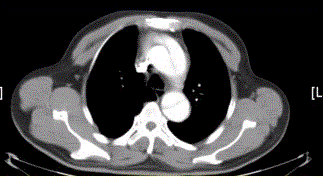

问题 患者男,67岁,高血压病史多年,自服降压药,突发胸骨后剧烈疼痛2h,服用硝酸甘油不缓解。胸透示主动脉增宽。CT影像如下图。 该例的影像学表现为

选项 A.主动脉增粗 B.主动脉内可见内膜瓣 C.真腔在左后方 D.假腔在右前方 E.假腔较小 F.升主动脉和降主动脉同时受累

答案 ABF

解析 ABF